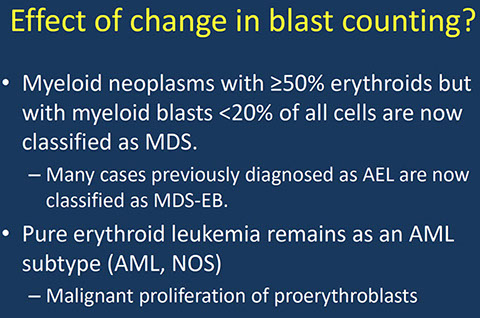

- Mild to severe anemia

- MCV and RDW usually elevated.

Dysplastic NRBCs, sideroblasts and siderocytes can be seen in the PB

- Reticulocyte count may be high or low.

<1% blasts in PB, <5% in BM